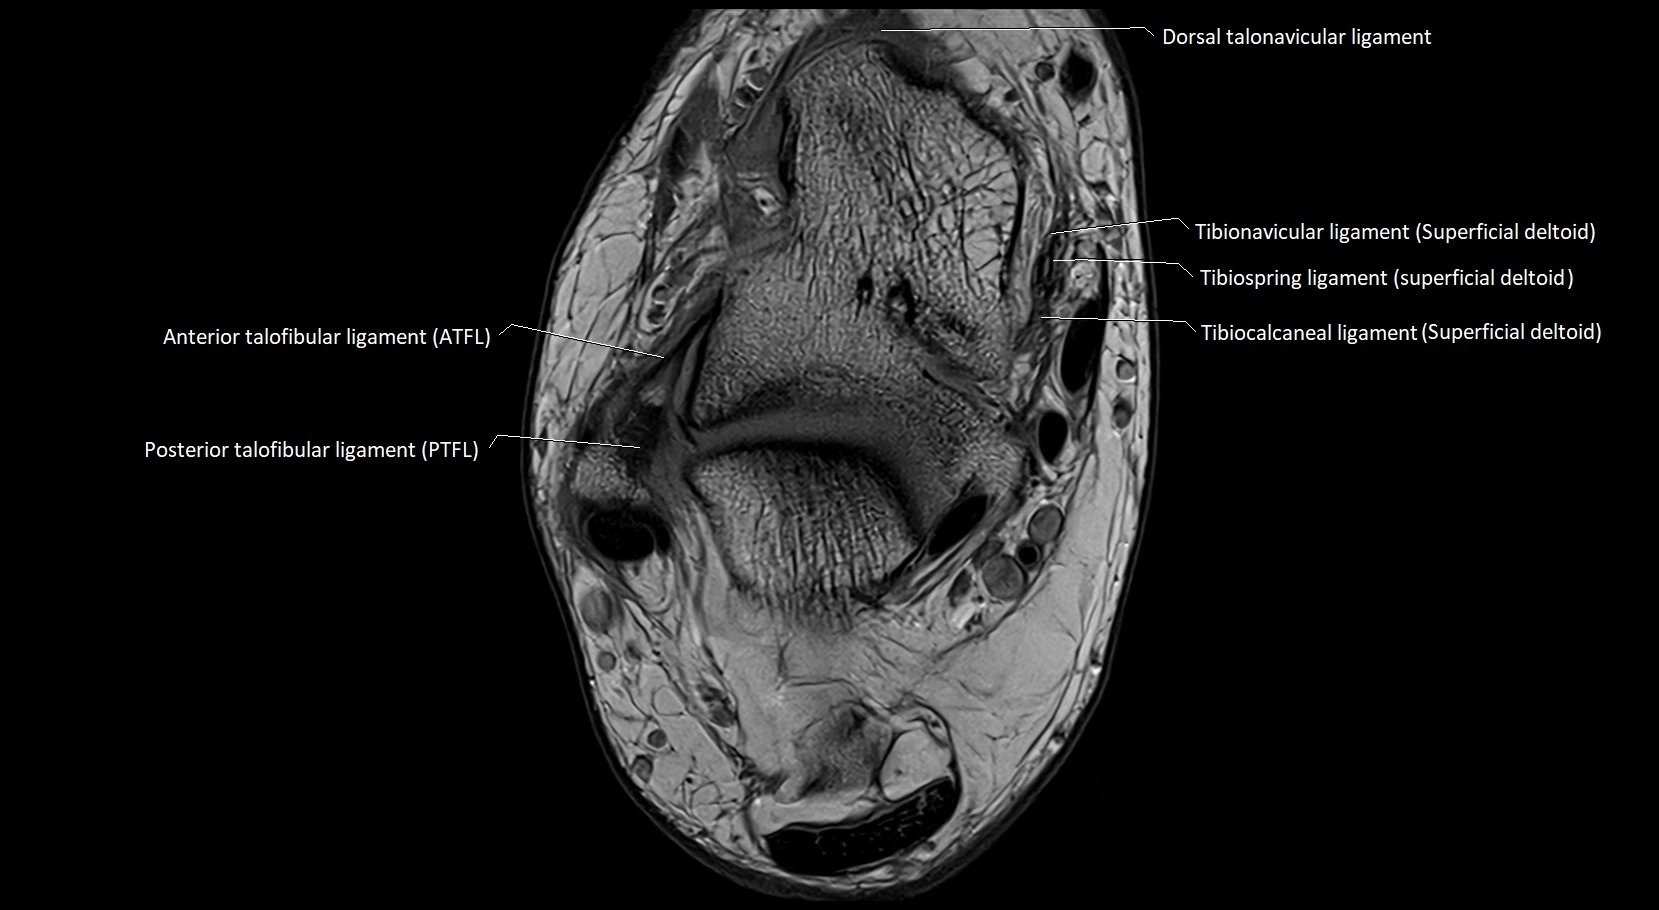

MRI image

image